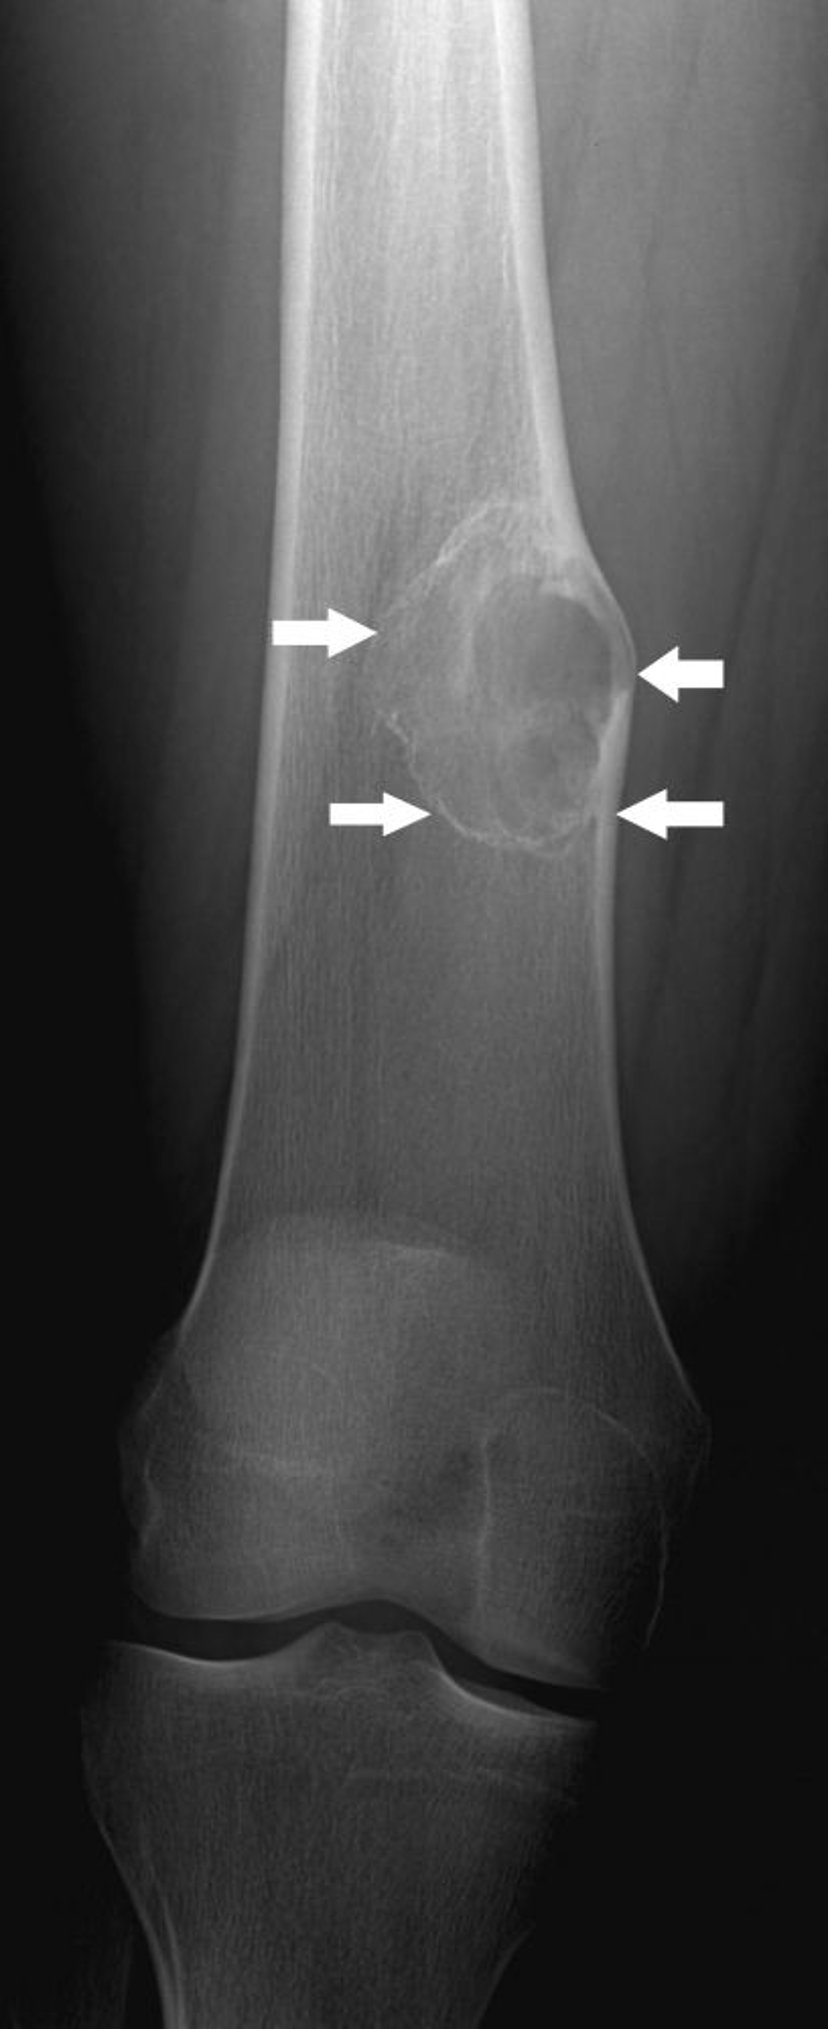

This radiograph shows a bone lesion (arrows) above the knee in the femur with mild expansion, which is typical of nonossifying fibroma.

Image courtesy of Michael J. Joyce, MD, and Hakan Ilaslan, MD.